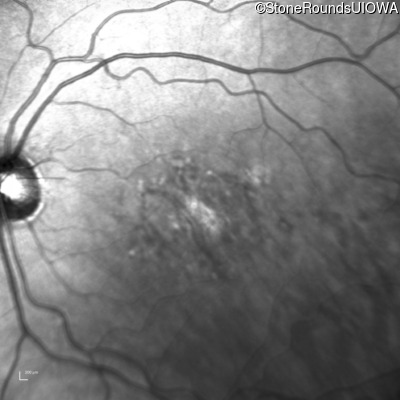

Infrared Fundus Photograph - Right - 20/125

Exemplar